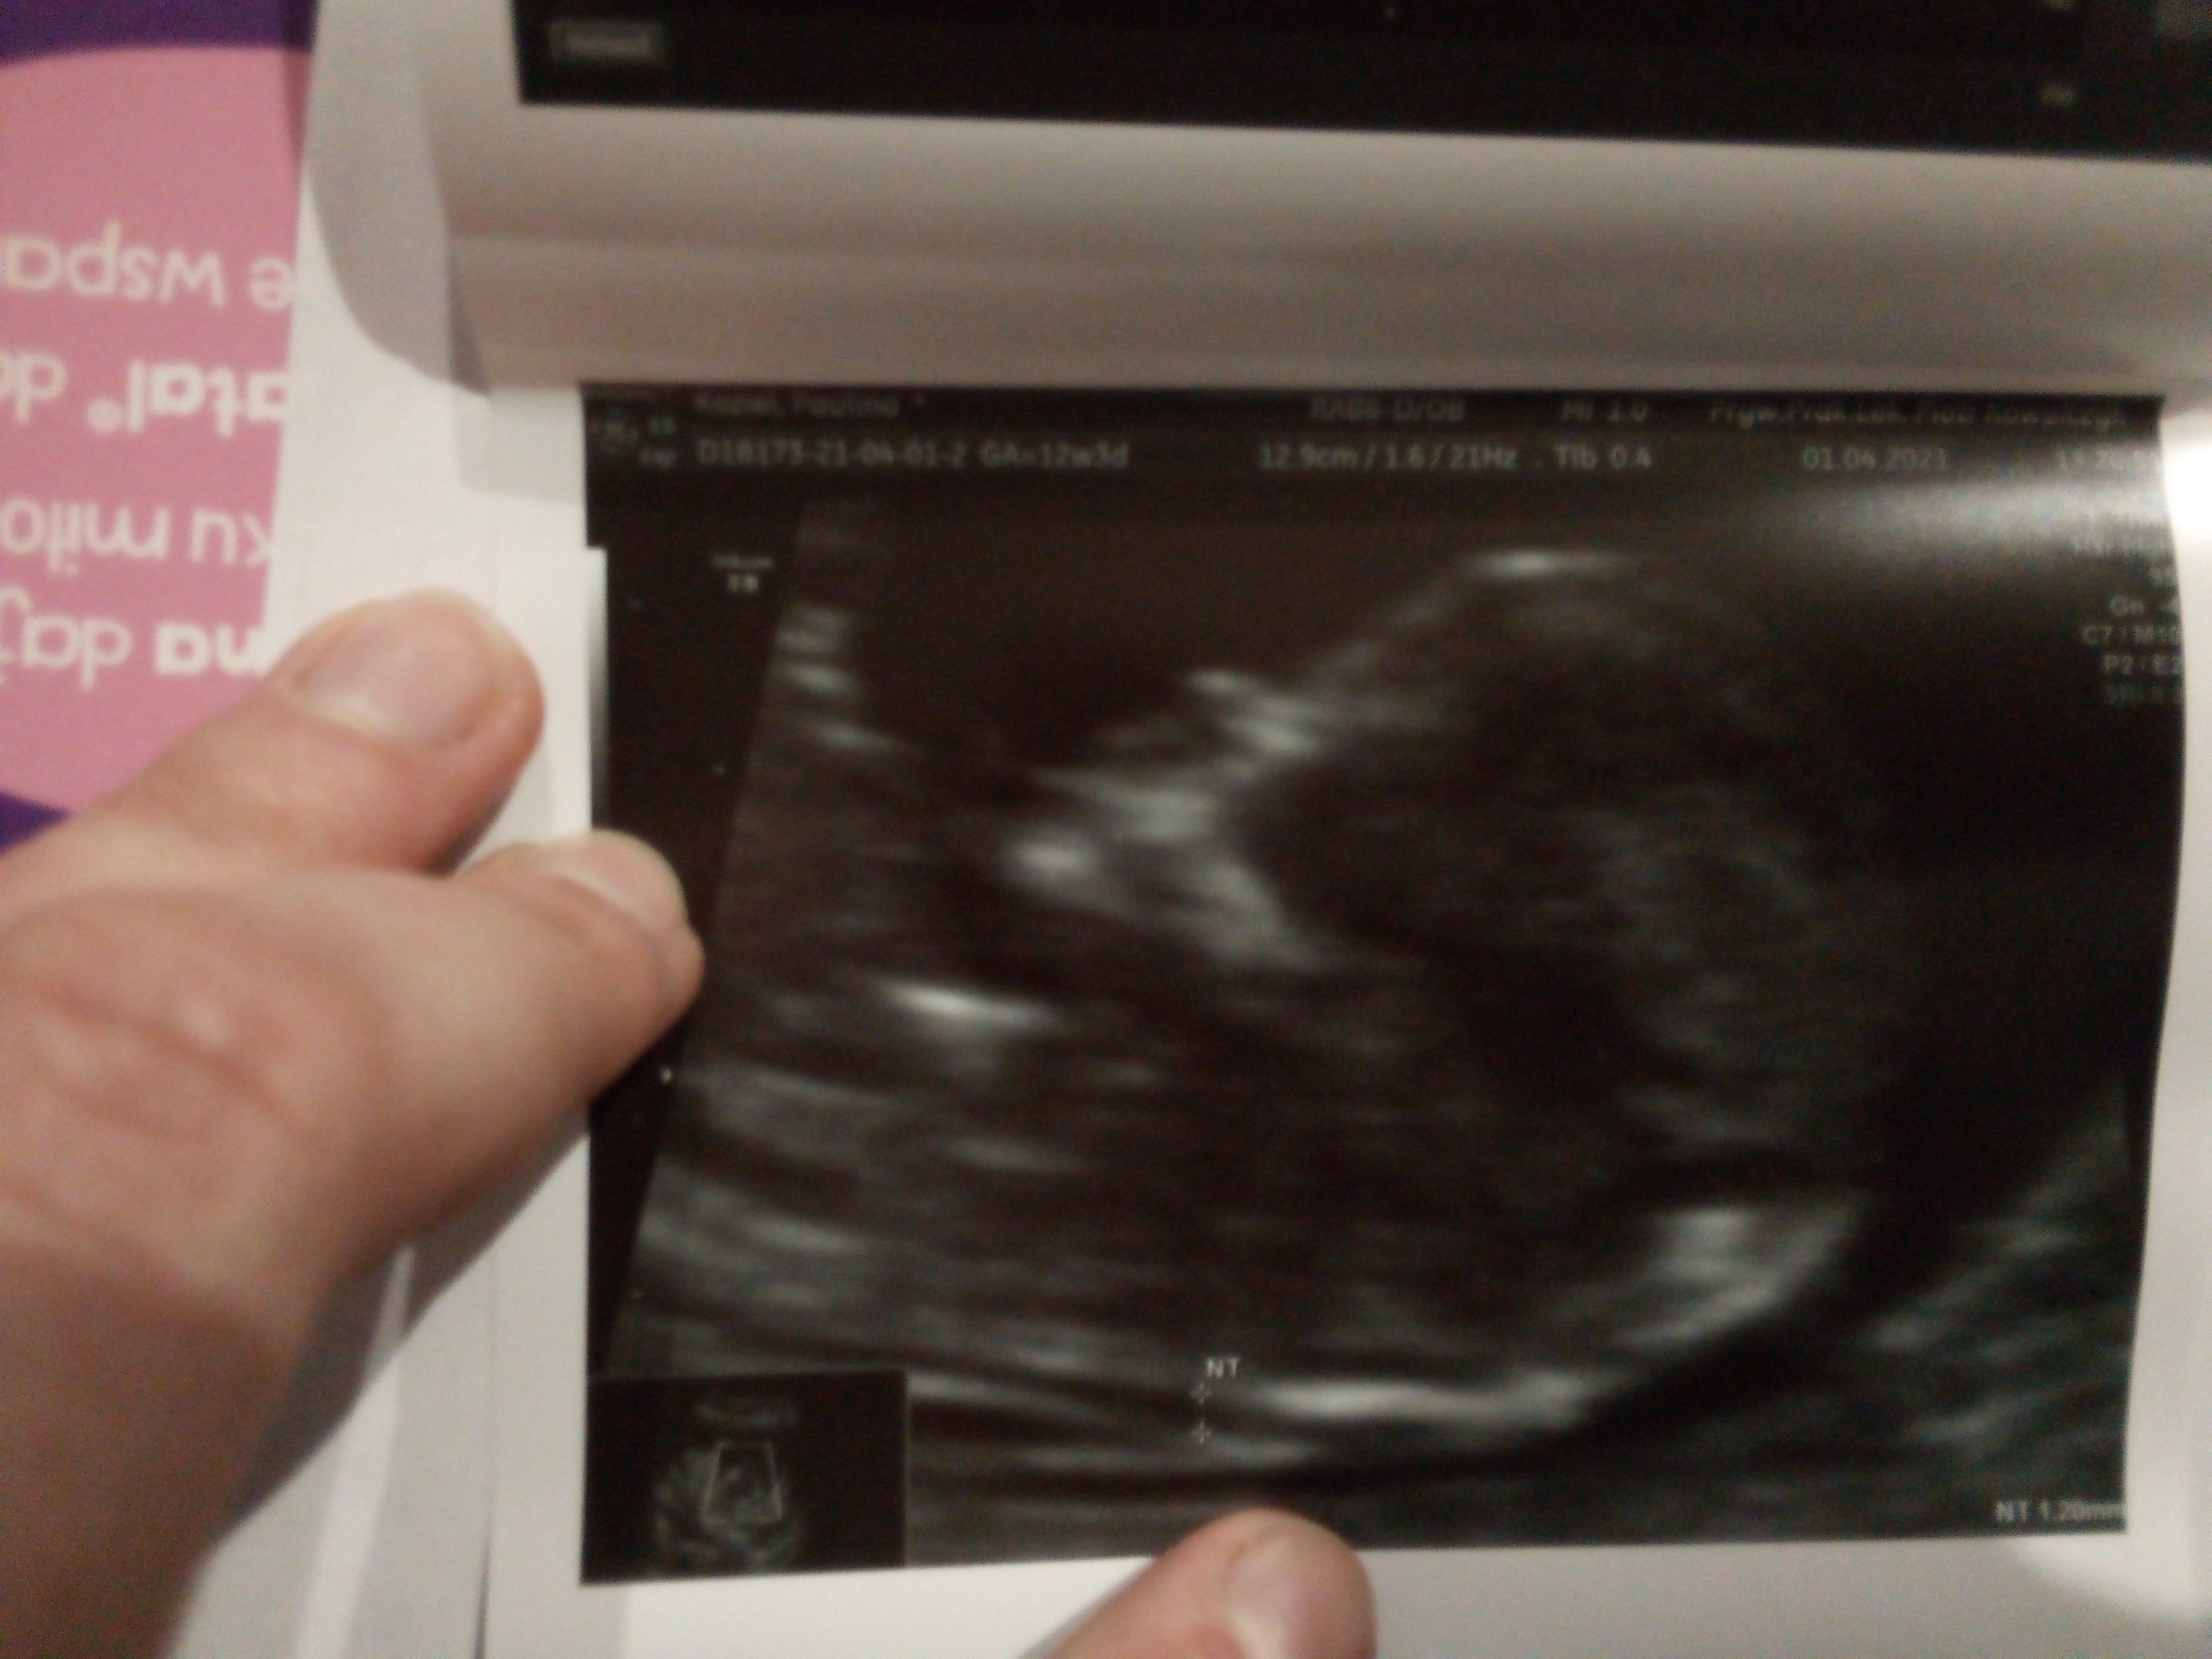

Nie wiem czy tylko ja tam widzę wyraźnie buzię?

Zdj. Z 1 kwietnia, USG prenatalnego.

Było ok 12 i pół tygodnia.

Wczoraj byłam znowu na zwykłej wizycie i już USG nie było tak wyraźne, więc przekonałam się na własnej skórze że nawet odrobina moczu w pęcherzu ma wpływ na obraz jaki widzimy. I teraz będę szła do toalety zawsze przed wejściem do gabinetu.![]()